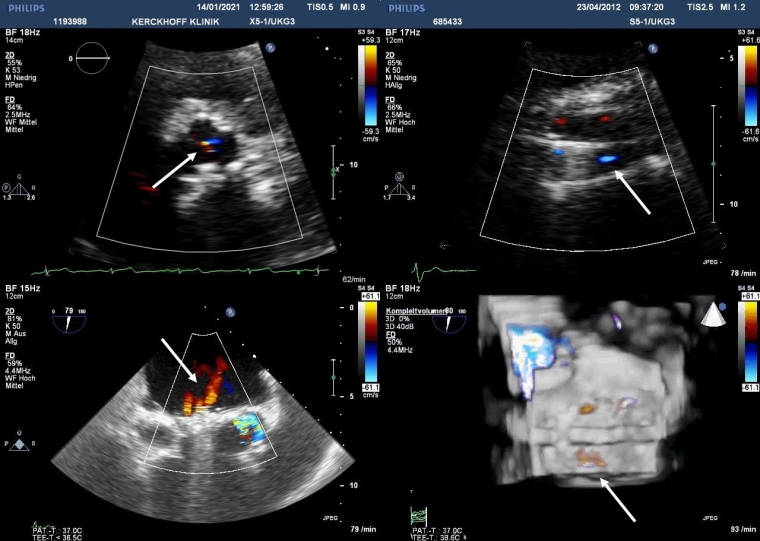

Prosthetic heart valves Part 3 Imaging Different Types Of Prosthetic Heart Valves Design of prosthetic heart valves focuses on four components: B, monoleaflet mechanical valve (medtronic hall); Broadly, they can be classified into three categories:. Improved optimal hemodynamics, mechanical/biological durability, minimizing biological response. A, bileaflet mechanical valve (st jude); What is an artificial heart valve replacement? An artificial valve is also known as a mechanical heart valve or a prosthetic heart. Different. Different Types Of Prosthetic Heart Valves.